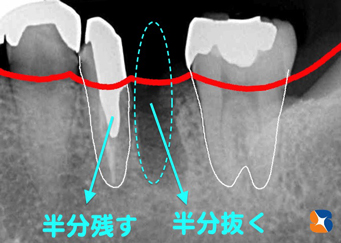

奥歯を2分割して良い方を残す

コラム「奥歯を2分割して良い方を残す」の画像